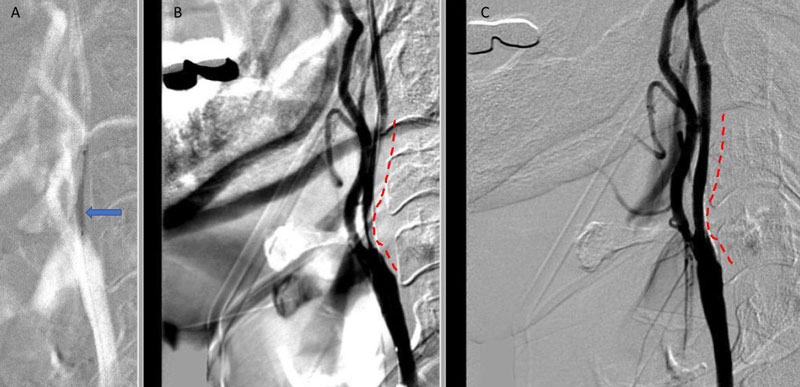

Catheter cerebral angiography was then performed which demonstrated the 99% stenosis with distal vascular collapse and extension of the plaque superiorly into the mid third of the cervical right ICA (Figure 4). Interrogation for collaterals from the left ICA and posterior circulations demonstrated very small and minimal contributions from the anterior communicating artery and posterior communicating artery of the Circle of Willis.

Figure 4. A) DS Angiogram demonstrates severity and extent of plaque to C2-3 level (blue). B) And marked delay of ICA perfusion (yellow) relative to ECA branches (green).